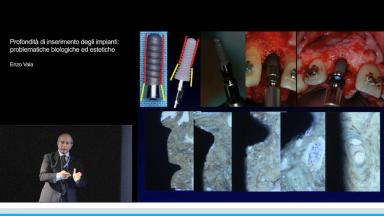

Profondità di inserimento degli impianti: problematiche biologiche ed estetiche

In questa presentazione vengono descritti gli effetti biologici e clinici di un incorretto posizionamento degli impianti. Il Dott. Enzo Vaia, dopo l’introduzione sulle caratteristiche bio-meccaniche delle superfici degli impianti e sui principi della chirurgia protesicamente guidata, affronta il tema del posizionamento tri-dimensionale dell’impianto con particolare rifermento alla profondità di inserimento. E’documentato in modo dettagliato come la posizione in senso corono-apicale sia un fattore determinante nel risultato di una riabilitazione implanto-protesica. L’argomento è presentato in modo chiaro ed esauriente con frequente menzione ai principi della Parodontologia per descrivere le problematiche biologiche inerenti agli impianti. Particolare attenzione è rivolta alla dimensione biologica peri-implantare come fattore chiave nel successo biologico, funzionale ed estetico a lungo termine.